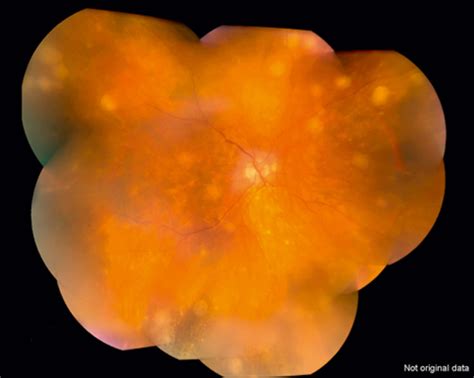

Dalen Fuchs nodules, also known as Fuchs' spots, are a distinctive feature of certain eye conditions, particularly those related to syphilis. These nodules are small, grayish-white lesions that appear on the retina, often in the posterior pole. Understanding Dalen Fuchs nodules is crucial for ophthalmologists and healthcare providers, as they can be indicative of serious underlying conditions that require prompt and appropriate treatment.

Dalen Fuchs nodules are small, round, grayish-white lesions that appear on the retina. They are typically found in the posterior pole of the eye, which is the central part of the retina responsible for sharp, detailed vision. These nodules are often associated with syphilitic uveitis, an inflammatory condition of the eye caused by syphilis, a sexually transmitted infection.